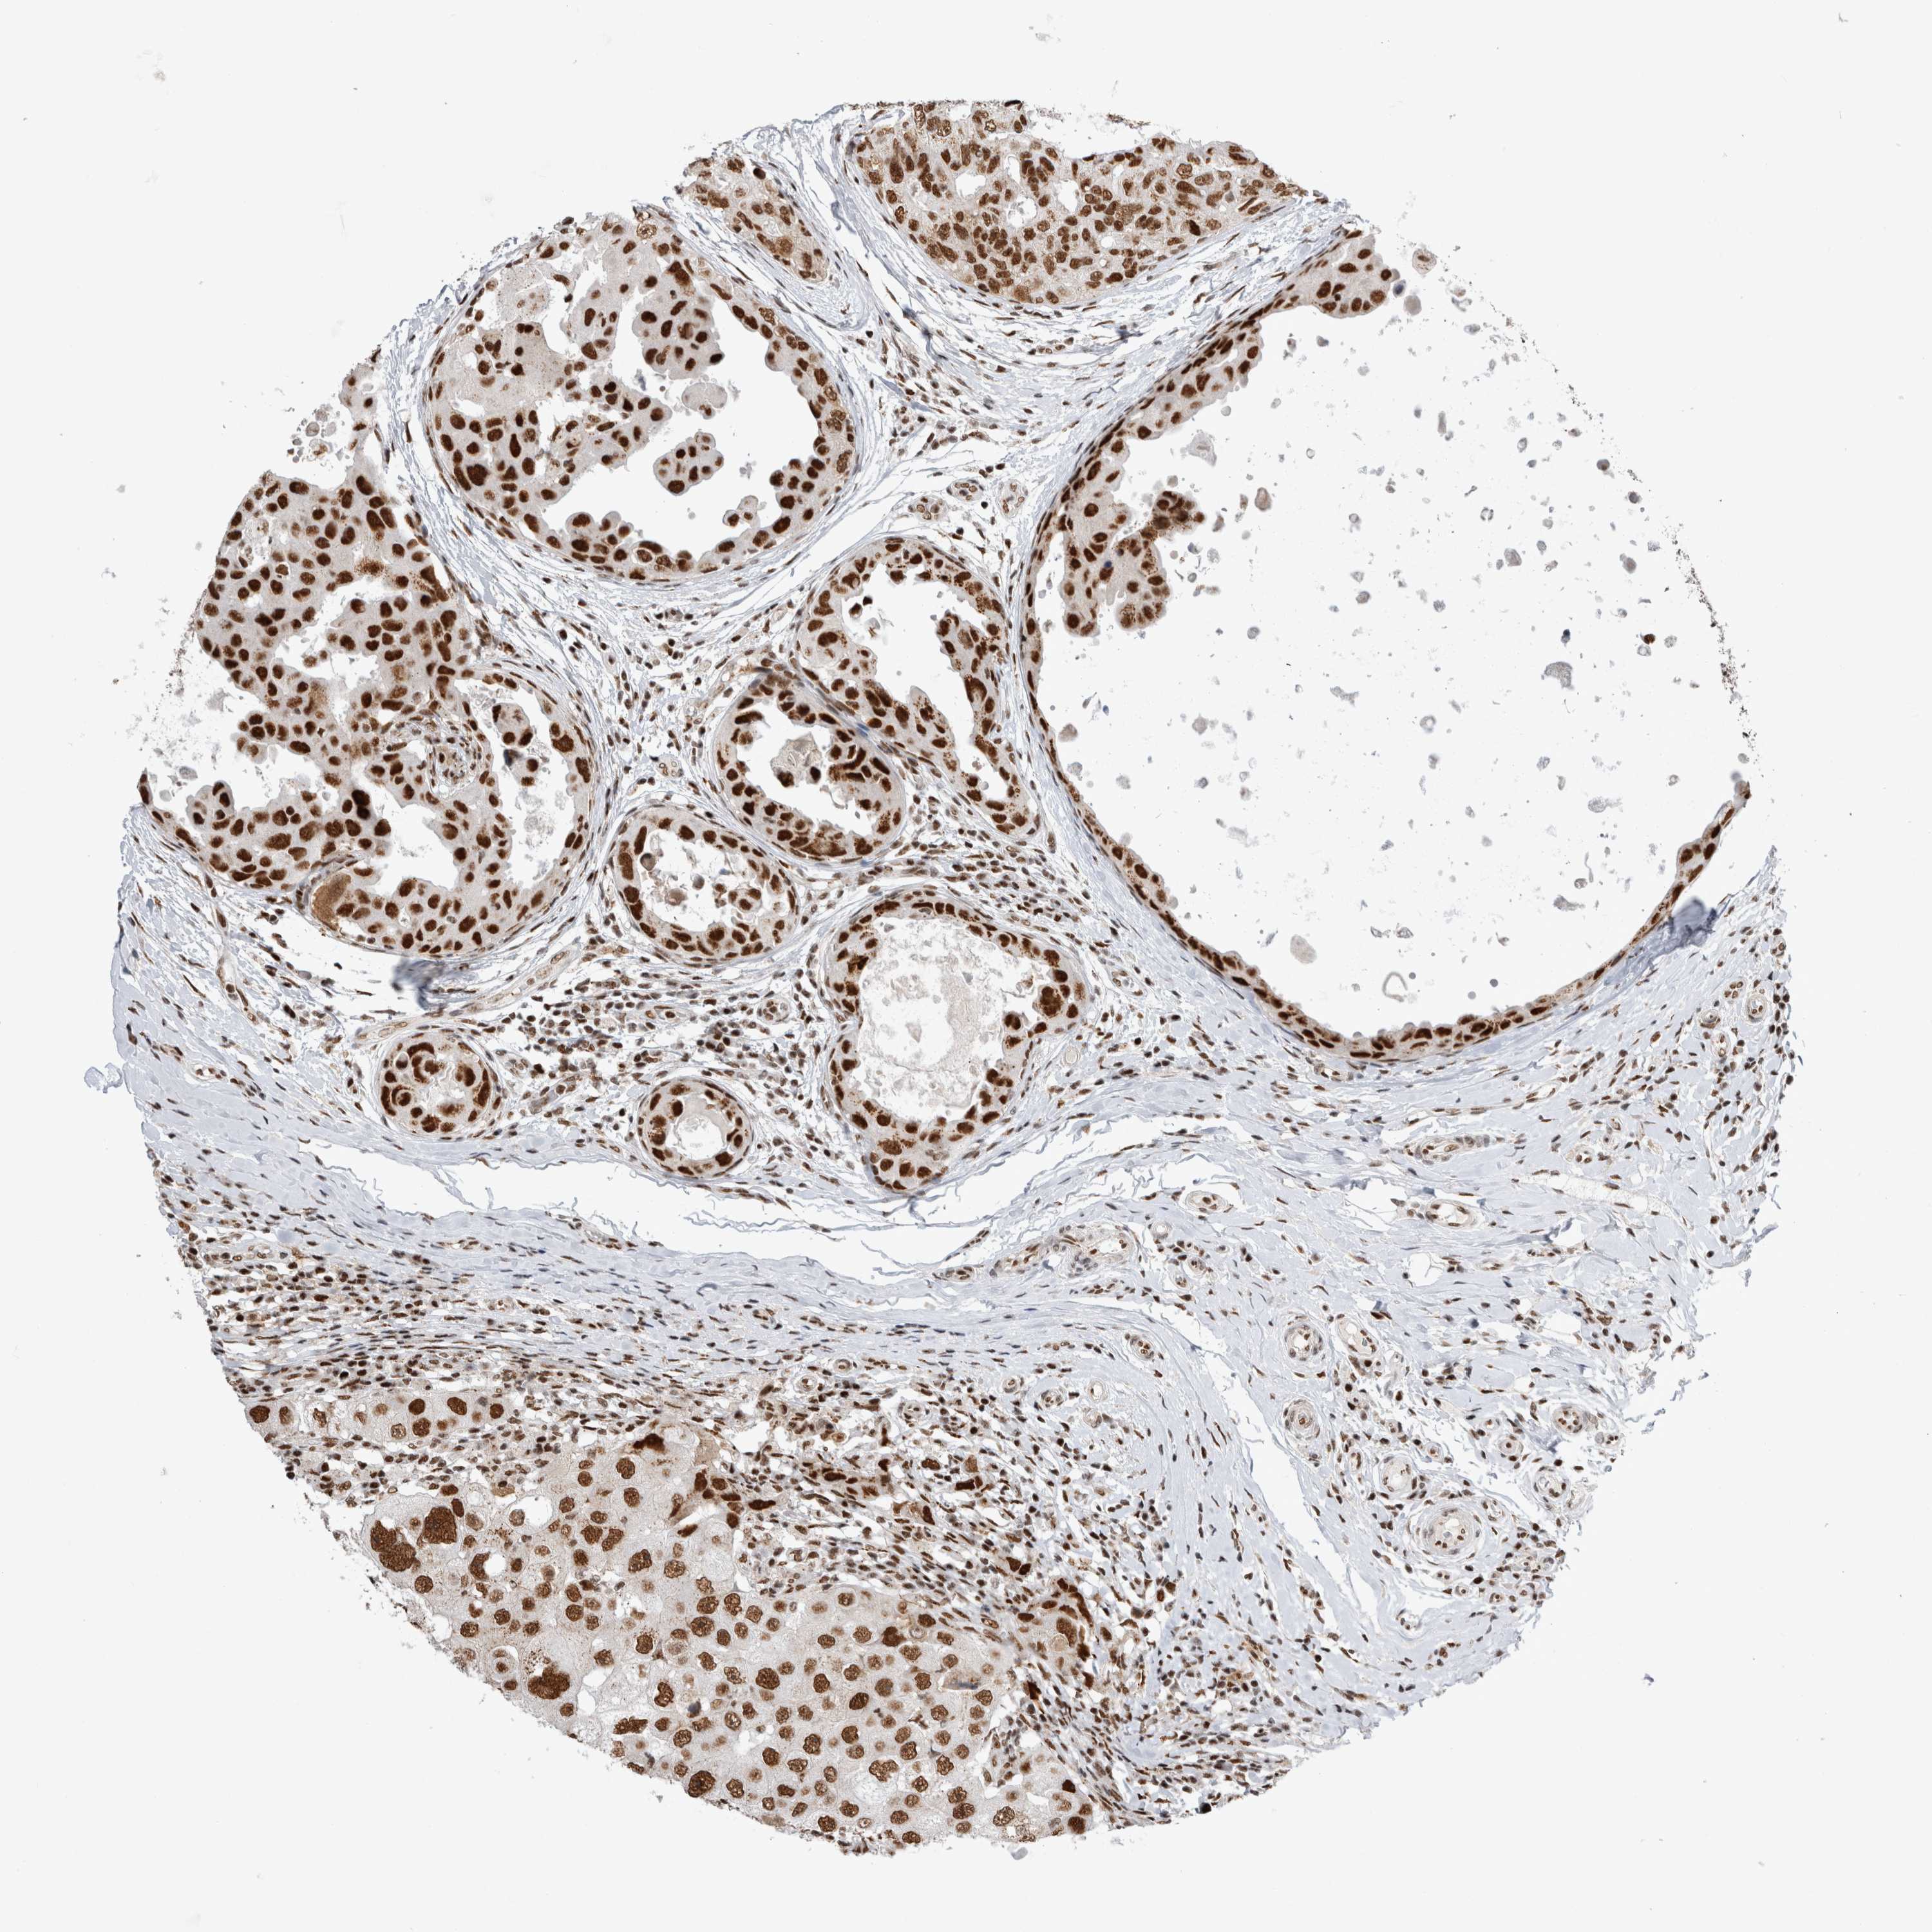

CANCER BREAST CANCER Show tissue menu

BRCA TCGA BRCA VALIDATION PROTEIN EXPRESSION